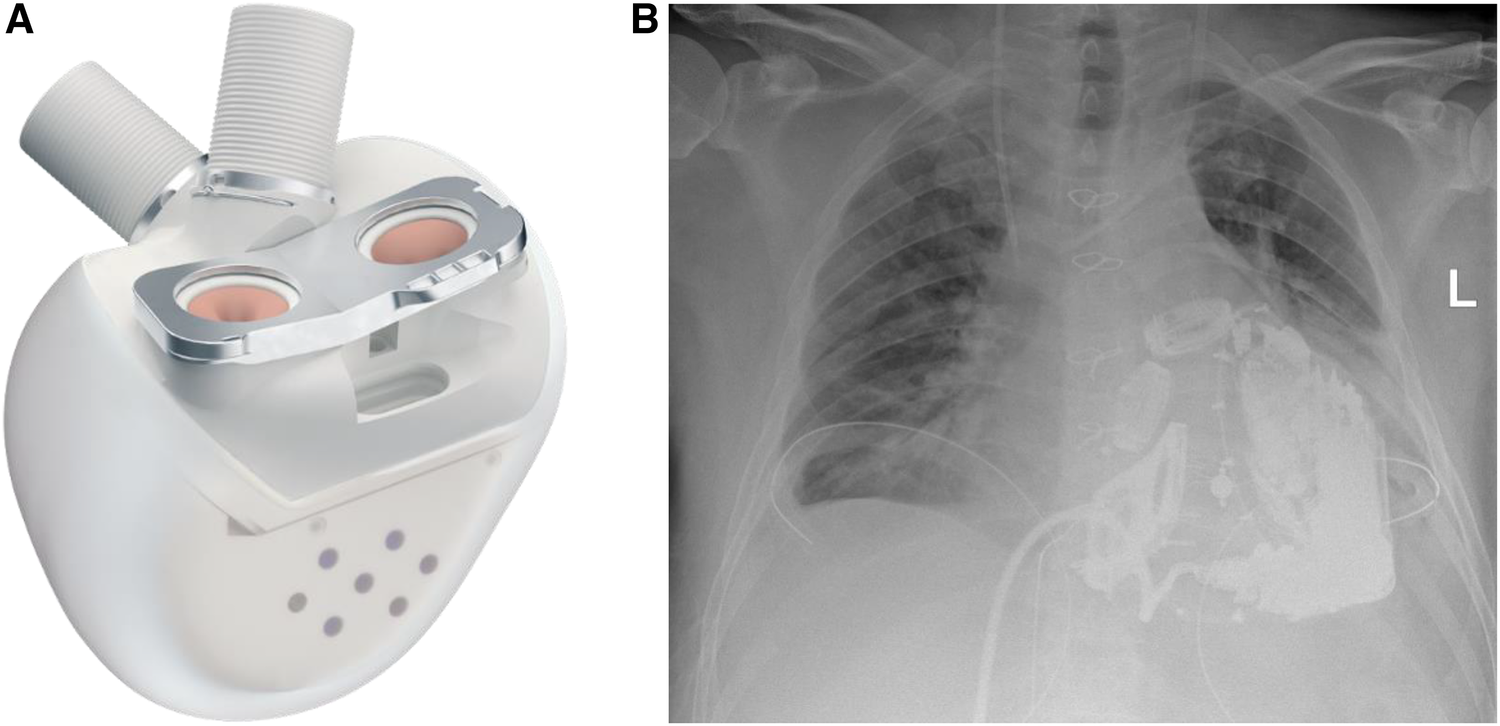

Figure 3

(A) The Aeson TAH device, courtesy of CARMAT (SA, Vélizy, France). (B) Chest x-ray of the patient after Aeson TAH implantation.

The surgical procedure started with a surgical preparation of the groin vessels followed by median sternotomy and aortic and bicaval cannulation. Cardiopulmonary Bypass (CPB) with central cannulation was initiated and the ECMO cannulas were removed surgically. At full CPB flow, the aorta was cross-clamped, as distally as possible. The native ventricles were excised one centimeter above the atrio-ventricular plane. To reduce the risk of air embolism, CO2 was flushed into the pericardial space. Two bioprosthetic atrial cuffs with central openings were sewn to the annuli with two layers of running sutures. A rectangular titanium interface was placed and secured to the cuffs. The Aeson device, mounted with four biological valves and two outflow conduits, was attached to the atrial interface (Figure 3). The Dacron outflow conduits were then connected to the pulmonary and the aorta with running sutures and re-enforcing patches. The driveline was tunneled through the right rectus muscle with skin exit at the lower right abdominal quadrant. The device was then connected to the portable controller. The TAH was first passively filled and de-aired with a vent placed in the ascending aorta. Pump beat rate and stroke volume were gradually increased while CPB support was weaned. Shortly after careful volume administration, the TAH was able to achieve stable cardiac output, and a substantial decrease in the catecholamines was achieved.